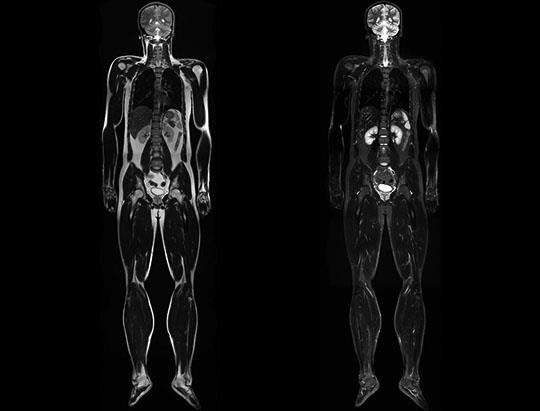

NCE-MRA of the Lower Extremity

Whole-body from Head to Toe